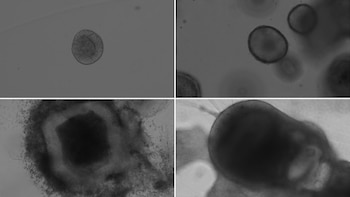

Los científicos prepararon ambos tipos de tejido en laboratorio y los expusieron al coronavirus SARS-CoV-2. “La observación directa con microscopía mostró el desarrollo de lesiones típicas de amiloide-beta en los organoides y en las retinas”, afirmaron.

Esto confirma que el virus, por sí solo, podría dar origen a placas asociadas a la enfermedad de Alzheimer en tejidos humanos.